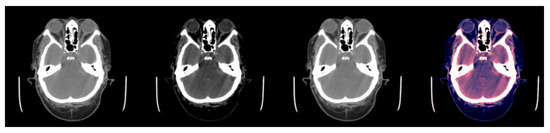

Figure 1 and Figure 2a illustrate the use of our model. An image where the model predicts bleeding (ICH) with a probability of 0.9897 is shown, and, in addition, Grad-CAM was able to determine the bleeding area to make that decision. Appendix A.2 provides a more technical description of this technique.

Figure 1.

Example of slice windowing as pre-processing of an HU matrix to obtain three different matrices (window used between brackets). From left to right: (1) slice with [0.80], (2) slice with [−20, 180], (3) slice with [−150, 230], (4) the three windowed slices stacked (each channel is associated to one color RGB for visualization purposes).

As our neural network took three channels (i.e., a RGB image) as input, the scans with the HU matrices had to be pre-processed to obtain three matrices of size pixels, one for each channel. To obtain these three matrices, three different windows were applied to every slice. Applying a window with X as lower bound and Y as upper bound meant that all HU values lower than X were converted to X, all HU values greater than Y were converted to Y, and the rest remained the same (see Figure 1).